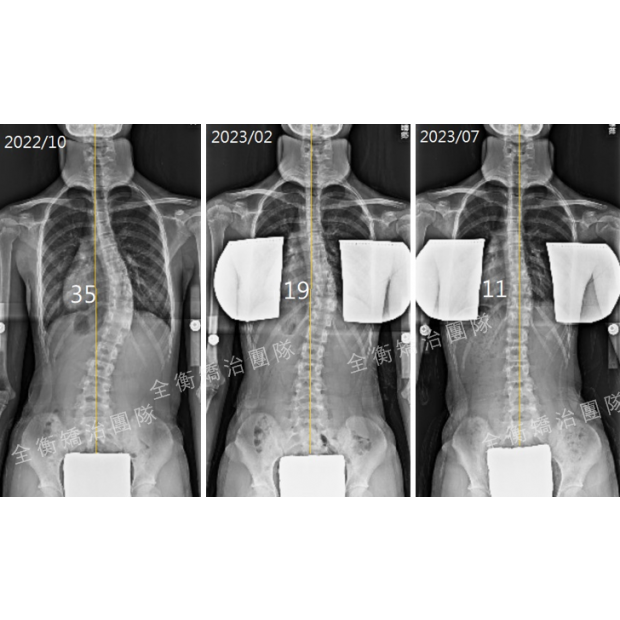

11嵗側彎女生矯正效果媲美手術的祕笈 : 對的時機+對的方法+確實執行11嵗側彎女生矯正效果媲美手術的祕笈 : 對的時機+對的方法+確實執行

11歲脊椎側彎女生,治療(背架+復健運動)半年後,胸椎大彎由45度改善至20度